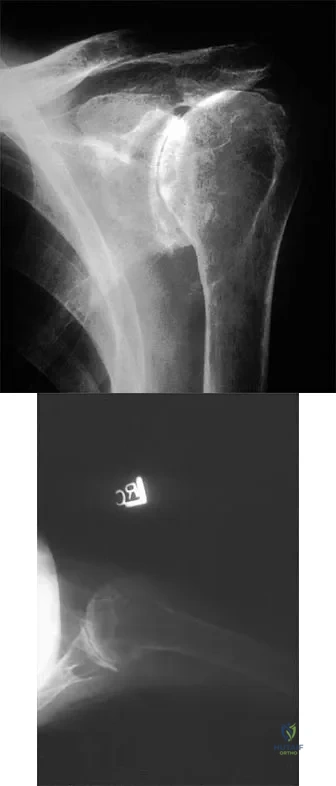

Question 92

A 55-year-old woman with polyarticular rheumatoid arthritis has had progressively increasing left shoulder pain for the past 2 years despite nonsurgical management. No focal weakness is noted during examination of the shoulder. AP and axillary radiographs are shown in Figures 47a and 47b. Treatment should consist of

Explanation